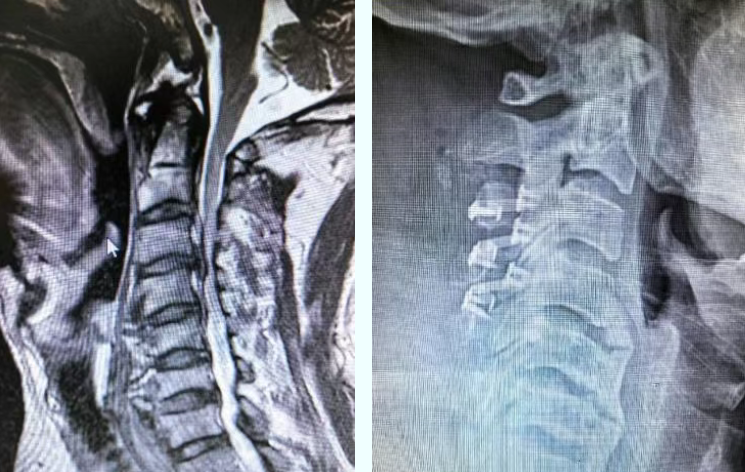

近日,医院外科团队成功为一名颈椎管狭窄症患者实施“后路颈椎单开门椎管扩大成形术”。该患者因长期四肢麻木、肌力进行性减退及步态不稳前来就诊。经详细检查,确诊为“颈椎管狭窄”,影像显示其颈3/4、颈4/5、颈5/6多个节段椎管严重狭窄,脊髓明显受压。如不及时干预,可能导致神经功能不可逆损伤,严重影响患者生活质量。

面对这一复杂病情,医院外科团队在王永福主任的带领下组织了严谨的术前讨论。经综合评估,团队最终决定实施目前国际推崇的“颈椎后路单开门椎管扩大成形术”。该技术如同在狭窄的椎管后方“开一扇门”,通过精细操作,将椎板一侧切开作为“门轴”,另一侧掀起作为“门板”,从而扩大椎管容积,为受压的脊髓神经“松绑”,解除压迫,同时能最大限度地保留颈椎后方结构的稳定性,具有减压充分、术后颈椎活动度影响小、长期稳定性好等显著优势。